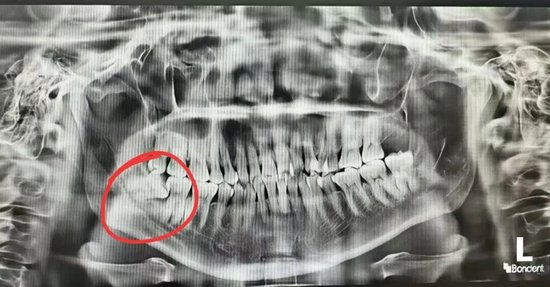

张女士的困扰由来已久,右下智齿不仅让她吃不下饭、夜不能寐,更让她痛苦的是一平躺就天旋地转,日常睡觉需垫三个枕头。然而智齿情况不容乐观,拍片显示智齿横向生长,牙根粗壮且紧贴下牙槽神经,一旦损伤神经,可能导致下巴、下唇终身麻木;加上张女士张口幅度仅能容纳两根半手指,常规平躺拔牙的操作方式在她身上完全行不通。